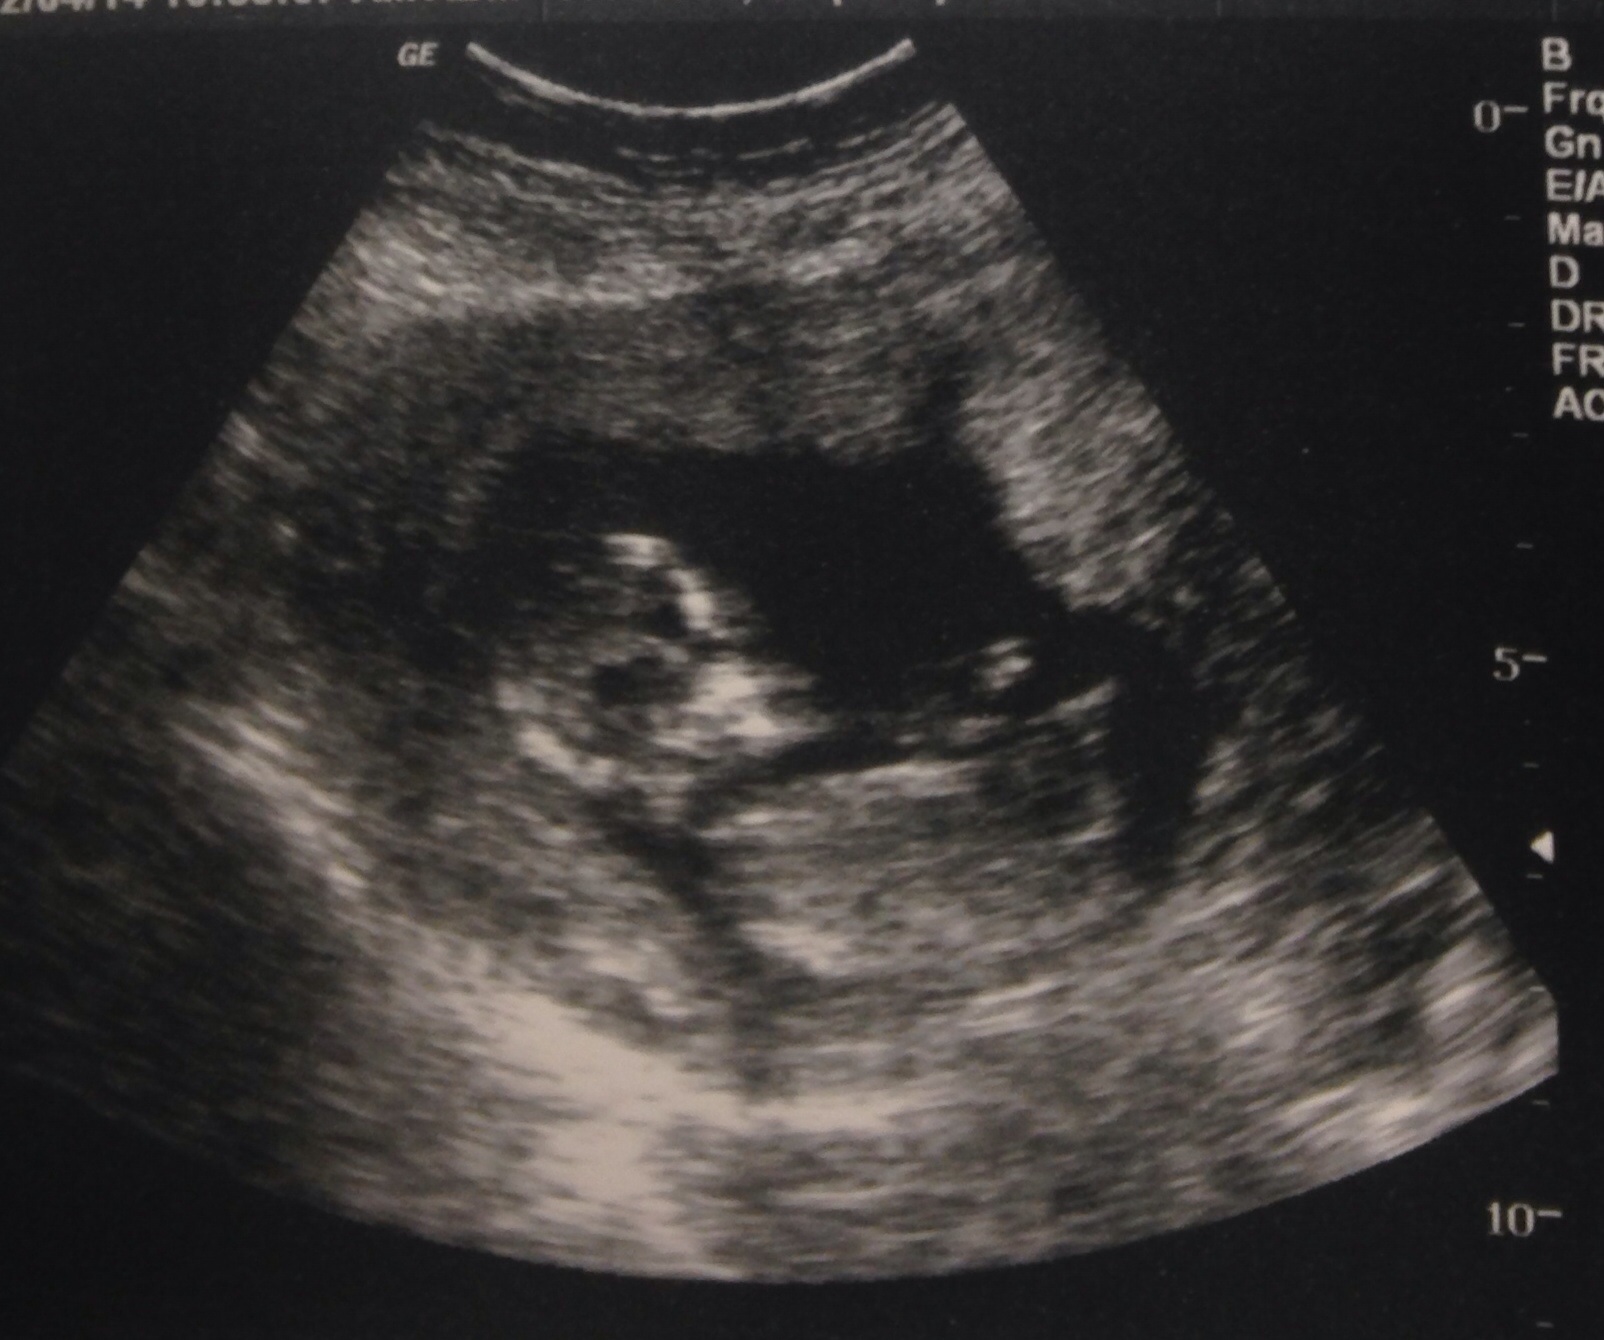

Thanks in advance for guessing! I'm new to this site and would appreciate any input. This photo is my from my 13 week scan. Thank you again...Attachment 16953

Any and all guesses greatly appreciated. Full disclosure: I have 2 boys

, so I'm hoping for a girl...

I never knew of the nub theory with mi boys, so this is my first time trying to use it. That's why I'm definitely in search of more experienced nub guessers ;-)

I am not an expert just enjoy guessing while I wait to find out what I am having. It does looked forked at the end but it's at an angle so I would guess boy. Just a guesss I hope I am wrong and you hear pink. Congrats

I'm no expert, but looking at the skull, it looks pink to me!!. I can't make out the nub.... sorry!!. Hope you hear pink. Good luck xx

I see a little fork at the midsection/lower section of her body.. I think it is a girly part.. Not an expert, just guessing : )